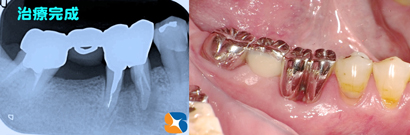

奥歯をメンテナンスしやすいように分割保存 奥歯を2つに分割して抜歯を回避しました。

ブリッジ 2分割したことで、今まで清掃が不可能であった股間部を、細い歯間ブラシで清掃可能となりました。装着して3年経ちますが、特に問題もなく、快適な食生活を送られているとのこと。